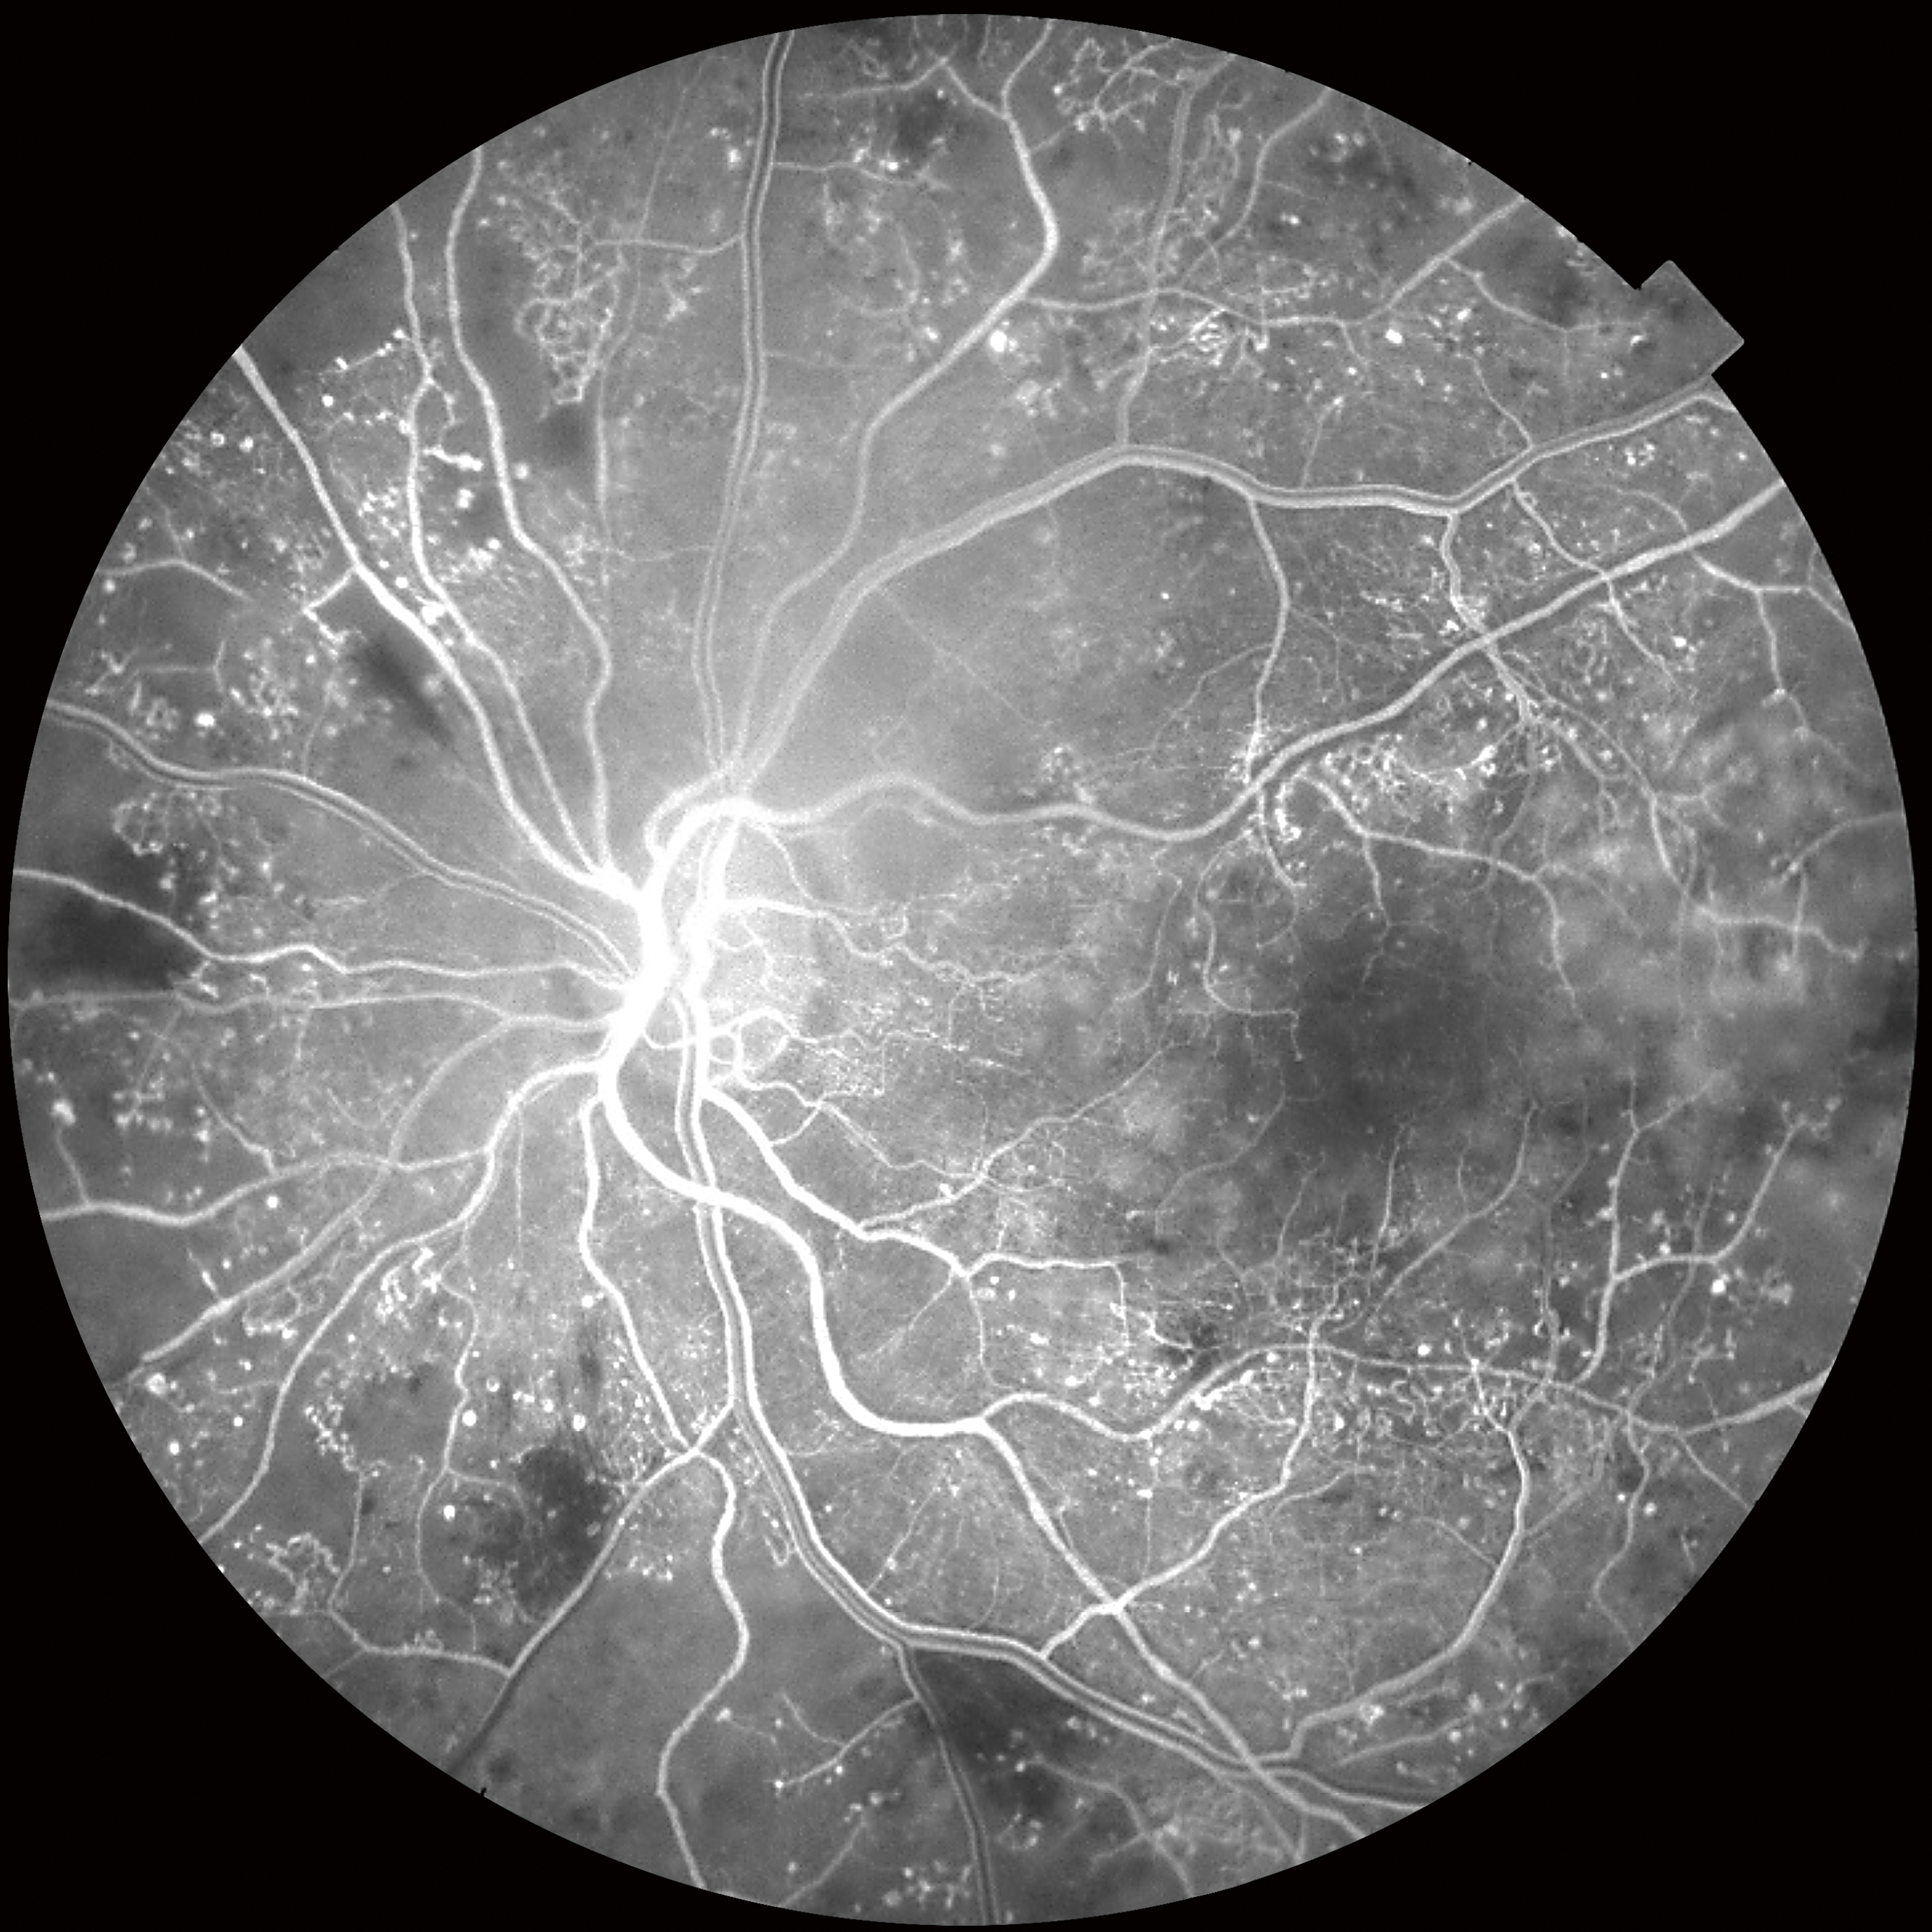

- Мультимодальная диагностика в одном приборе: совмещение фундус-камеры с ОКТ (модель DRI Triton), а также с ФАГ и автофлуоресценции (модель DRI Triton plus)

- Модуль ОКТ-ангиографии

Помимо ОКТ и ОКТ-ангиографии прибор позволяет получить снимки глазного дна с помощью встроенной немидриатической фундус-камеры. Модель DRI TRITON plus оснащена также модулями флуоресцентной ангиографии (AF) и автофлуоресценции (FAF).